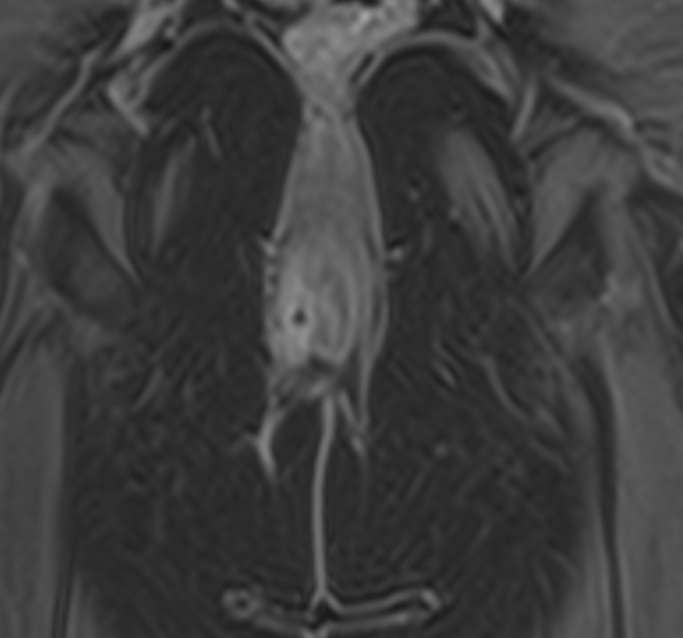

МРТ аноректальной области с контрастным усилением – это специализированное исследование, используемое для детального изучения структур и патологий в области ануса, прямой кишки и окружающих тканей. Контрастное усиление помогает улучшить видимость кровеносных сосудов и определить границы патологических образований.

Преимущества МРТ аноректальной области включают высокую детализацию мягких тканей и отсутствие ионизирующего излучения. Контрастное усиление помогает лучше визуализировать сосуды и патологические изменения.

В целом, МРТ с контрастным усилением является безопасной и информативной процедурой для диагностики различных заболеваний аноректальной области.